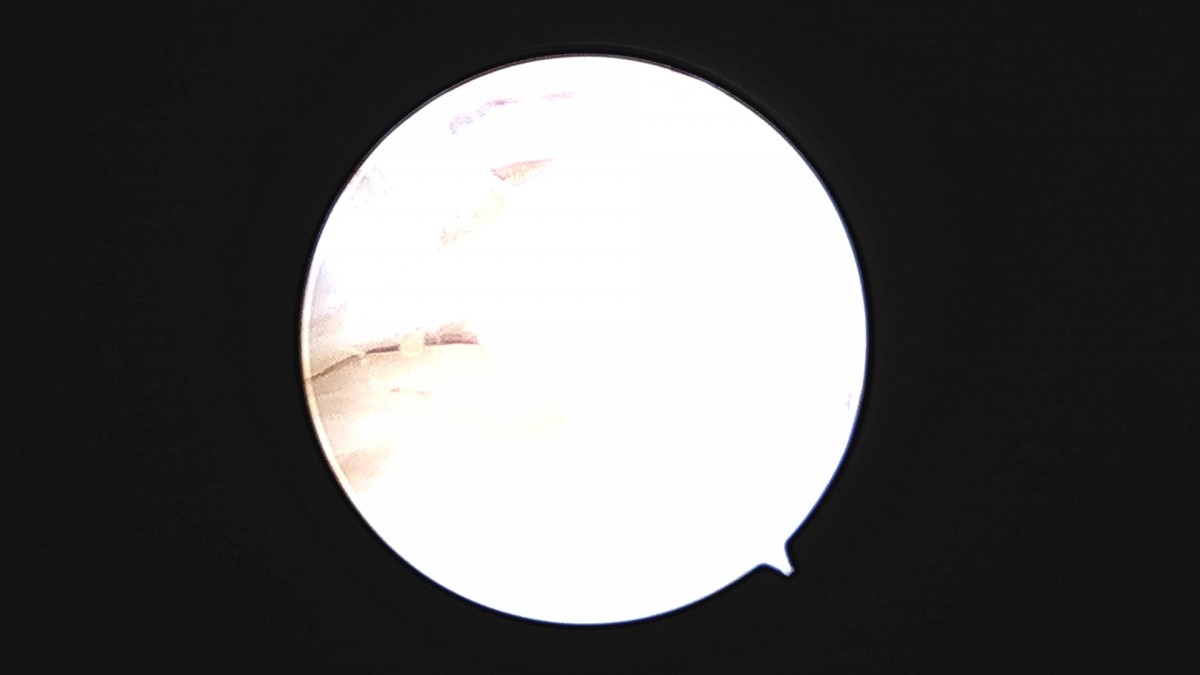

이재상원장님 발목 연골병변 제거술 및 골수 자극술 장경O 환자

작성자 최고관리자 댓글 0건 조회 375회 작성일 25-09-16 16:14